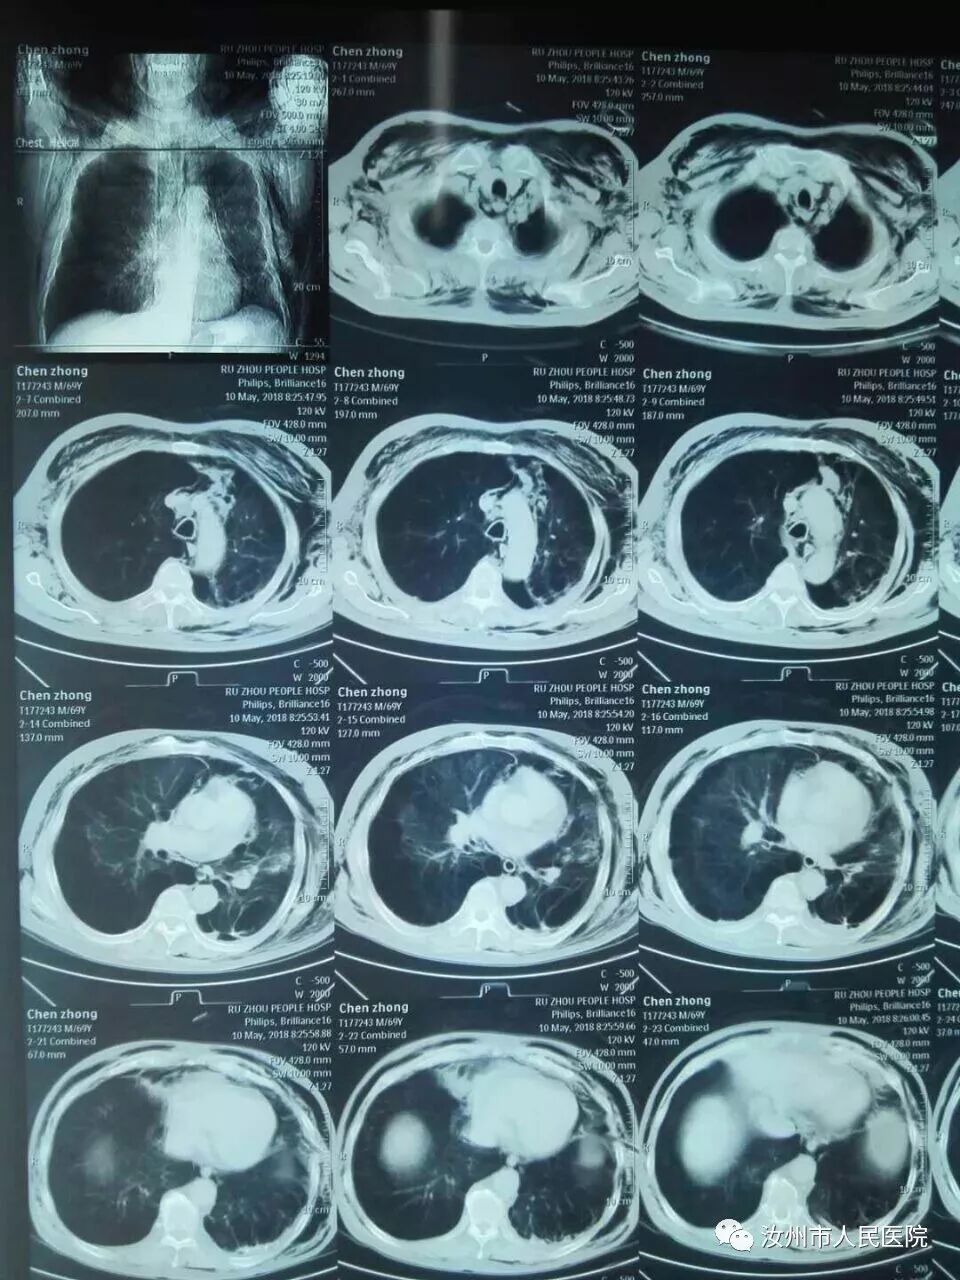

七十岁家住蟒川乡的陈老先生,曾患慢阻肺数十年,平时有间断性胸闷气短及呼吸困难等症状,长期口服药物控制。近2月症状日渐加重,遂来我院检查,查CT示:慢性肺气肿伴肺大泡形成,左肺巨大肺大泡形成。以“慢阻肺并肺大泡形成”收入我院外科二病区

为进一步保证患者的手术治疗效果,特请来了省医的专家做指导,经过严谨的术前准备,2018年5月5日,手术开始备好胸腔镜物品,连接、检查及调节胸腔镜摄像系统,电切割系统和手术器械。先用尖刀片切开皮肤,电刀止血,依次切开胸壁各层组织,在腋中线第8肋间做一个12mm长切口,,置入10mm穿刺套管。置胸腔镜镜头于穿刺套管内观察胸腔。在内镜的监视下于腋前线第4肋间做一切口,置入10mm穿刺套管,经该套管置入肺钳,钳夹肺叶组织。再于肩胛线第7肋间做切口,置入5mm套管,经该套管放入胸腔镜操作器械,根据胸腔镜探査结果,在肺大泡根部钳夹,用直线切割器和七号丝线钳夹、结扎。最后彻底检查手术野,生理盐水冲洗胸腔。肺膨胀后于腋中线第9肋间置入胸腔引流管,持针器夹持三角针7号丝线缝合切口并固定引流管,覆盖切口。在历经两个小时之后,手术顺利结束,手术很成功,术中出血少,切口也小。麻醉复苏后,病人安全返回病房。术后复查CT显示:巨大肺大泡消失。病人及家属对治疗效果非常满意。

图一为病人术前CT,左肺巨大肺大泡。

图二为病人术后复查CT,巨大肺大泡消失。